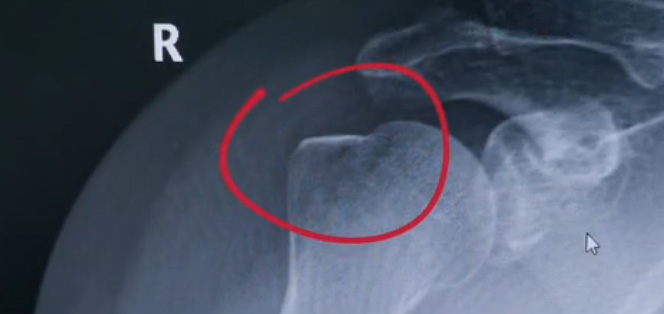

肩关节的X射线片子,看到没有明显的骨折,但是实际上已经骨折了。那么是如何发现的呢?医生对于做出疾病诊断的时候,会选择什么样的检查方式。也更好的配合医生,来解决问题。1米高的地方摔了下来,右侧肩关节与地面相撞受伤了。当时的胳膊还能活动,疼痛感很明显,但是在家观察了一天,这个肿胀没有明显的加重。然而问题是什么呢?疼痛始终不能缓解,所以就需要到医院检查。医生查看关节的受限也很明显,尤其做外展这个动作的时候,几乎没办法自行完成。肩关节内的这个韧带和肌腱可能还没有发生严重的损伤。

首先做一个普通的X光检查,看一看有没有大的骨折或大的问题。结果是没有发现太严重骨折损伤问题。结合病史,还是有点疑惑。因为疼的太厉害。x光检查和他的疼痛之间不匹配,患者没有骨头的损伤,疼痛不至于达到这么严重的一个程度。是否有一种情况掩盖住了病情。这也是X线检查的通病。x光检查它是一个二维的检查,有可能患者肩关节啊发生了骨折。但是它的位置被前方或者侧方的这个骨头遮挡住了。不是立体的就没办法看到后方的情况。想要更加进一步的明确问题,判断是否有骨头的损害怎么办?

进一步就是查CT,可以更全面的角度去判断问题的所在。就会发现是否骨折可以看到确实存在着骨折,还好骨折不算严重。可以说是一个骨裂。这个肩关节与地面撞击的时候,暴力没有达到那么强。让骨头整个发生一个巨大的断裂,而是造成了一个小的劈裂。适当的进行一些抗炎止痛药的使用。适当的进行一些消肿治疗,患者症状也就消失了。